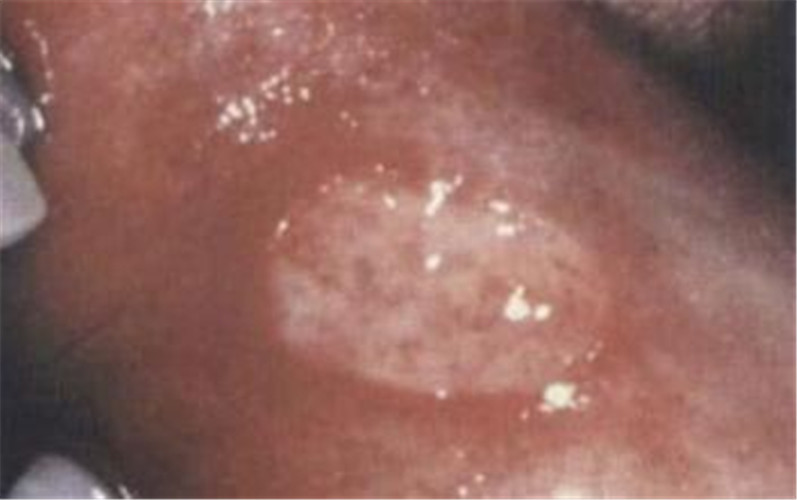

白塞病嘴唇處

白塞病嘴唇起泡

白塞病早期嘴唇